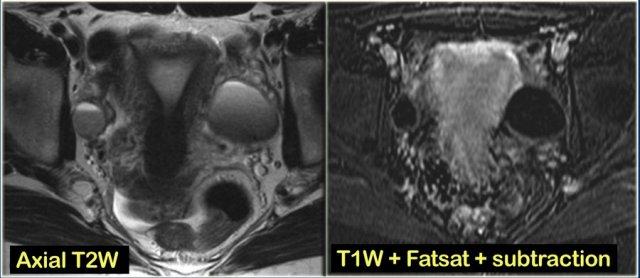

Trên MRI, nang xuất huyết tăng tín hiệu trên chuỗi xung T1-FatSat trước tiêm thuốc tương phản từ, và giảm tín hiệu trên T2.

Hình ảnh chuỗi xung T2W mặt cắt ngang và mặt cắt đứng dọc của cùng một bệnh nhân.

Buồng trứng phải chứa nhiều nang đơn giản tăng tín hiệu T2 với bờ mỏng và không có thành phần đặc.

Trên hình mặt cắt ngang, có một tổn thương giảm tín hiệu T2, tức là nang phức tạp (mũi tên).

Trên chuỗi xung T1W không có kỹ thuật xóa mỡ, nang phức tạp tăng tín hiệu, gợi ý thành phần mỡ hoặc máu.

Trên chuỗi xung T1W có kỹ thuật xóa mỡ, tổn thương vẫn tăng tín hiệu, loại trừ tổn thương chứa mỡ.

Sau khi tiêm Gd, không có ngấm thuốc, xác nhận đây là nang buồng trứng xuất huyết.

Lạc nội mạc tử cung dạng nang (endometrioma) cần được đưa vào chẩn đoán phân biệt.

Lưu ý rằng hình ảnh trừ (subtraction) là tốt nhất để chứng minh sự vắng mặt của ngấm thuốc trong tổn thương tăng tín hiệu trên chuỗi xung T1W trước tiêm thuốc tương phản từ.